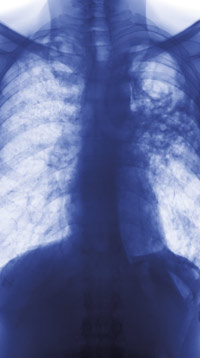

Pyrazinamid hemmer den bakterielle mekanismen trans-translasjon, som er viktig for overlevelsen av Mycobacterium tuberculosis.

Pyrazinamid brukt i kombinasjon med andre tuberkulostatika bidrar til kortere behandlingstid ved tuberkulose. Pyrazinamid omdannes til den aktive metabolitten pyrazinsyre av et mykobakterielt enzym, men den videre virkningsmekanisme er ikke klarlagt. Nå har en internasjonal forskergruppe studert molekylære effekter av pyrazinsyre i M tuberculosis (1).